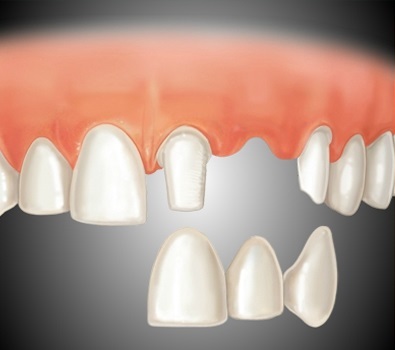

2. Egy megbízhatóbb lehetőség - a helyreállítása a koronát a sapkákat.

Ez a módszer akkor tekinthető megbízható és tartós. Protézisek elvégzett több látogatást körülbelül 1-1,5 hét. Állapotától függően a foggyökér élettartam - akár 10 év.

3. hidak - a legmegbízhatóbb, tartós megoldás.

Ezzel a módszerrel a helyreállítási fogazat hiba, a szomszédos fogak földre a koronát.

A leginkább esztétikai koronák koronát cirkónium-dioxid.

Élettartam híd 5 -15 év állapotától függően a felfekvési fogak.